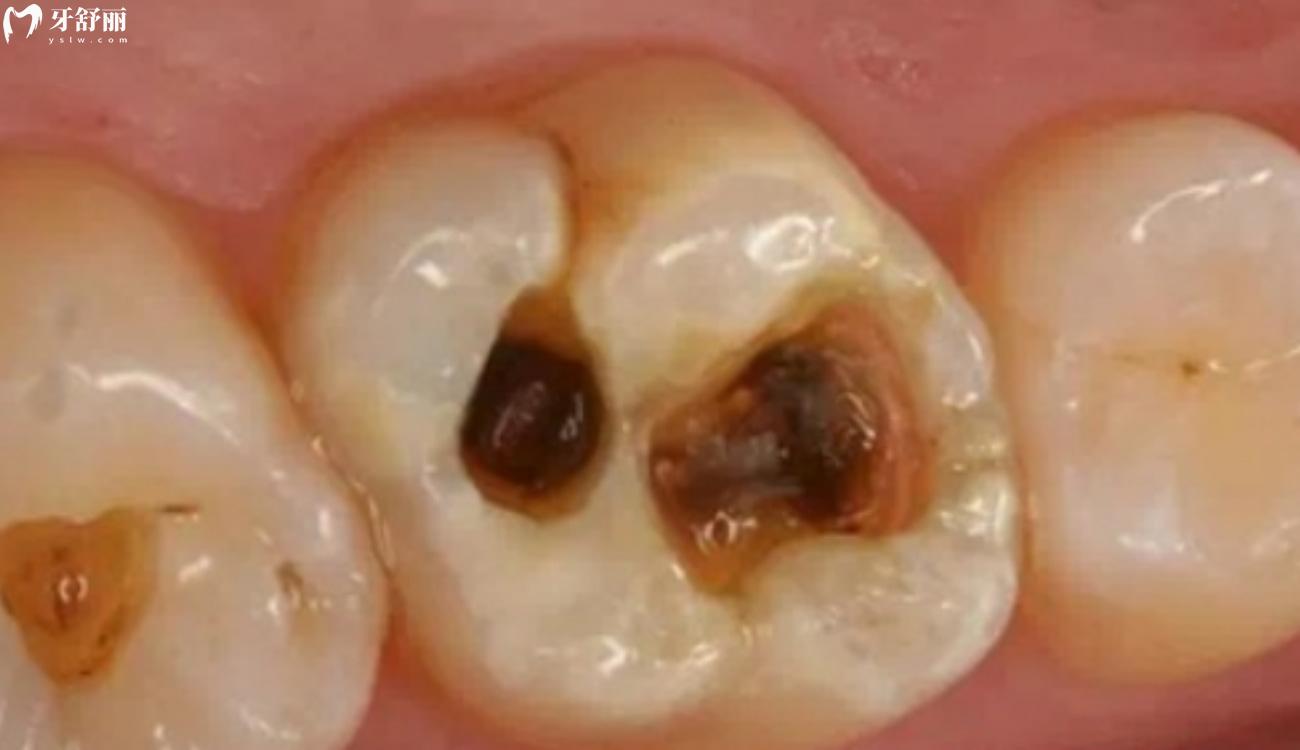

牙齿坏了一半里面都空了怎么办?补牙能治好吗?牙齿坏了一半里面都空了这样的情况可以到医院进行详细的检查,看看牙齿具体的情况,可以根据情况选择补牙、拔牙等处理方式。至于说补牙能不能治好?就要看牙齿的检查情况了,在平时我们要能够定期进行口腔检查,有问题及时发现,就是预防这样的情况发生。

如果检查之后可以进行补牙治疗,这说明检查结果还是比较不错的额,牙齿虽然坏了里面都空了,但是牙根比较的完整,有保留的价值,通常可以通过根管治疗以后,用树脂材料补牙的方式改善,在补完牙齿之后可以做上烤瓷冠或者是全瓷冠保护牙齿。

如果是牙齿坏了一半里面都空了的情况,属于龋坏程度较高的大面积的缺损的患牙,牙体修复后往往由于牙体组织抗力不足,在咀嚼时容易发生劈裂。所以要及时的做冠修复,防止牙齿劈裂。